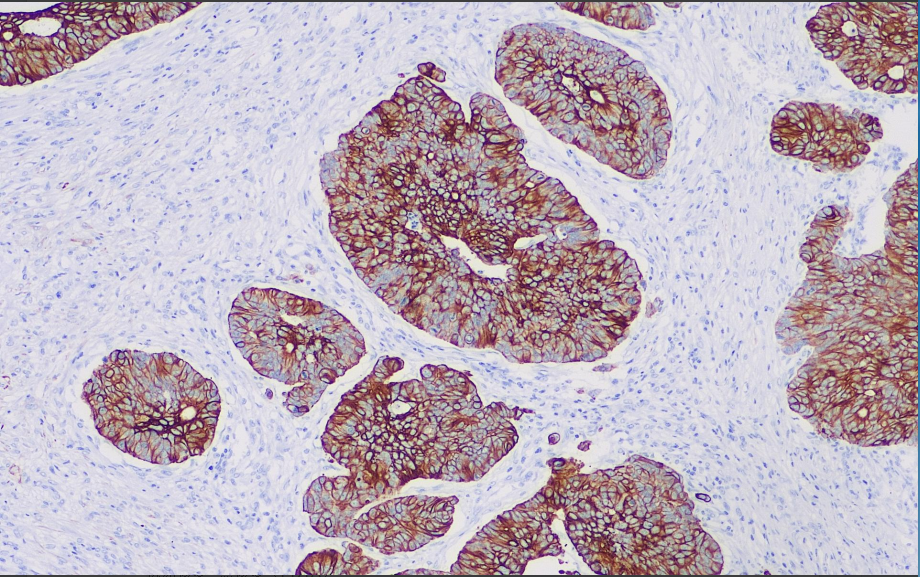

Positive control: Colorectal cancer

CK19 is present in normal epithelium and tumors of various epithelial origins, especially monolayer epithelium and mesothelium, and is negatively expressed in adult skin, hepatocytes, and cornea, while it is positively expressed in uterine epithelium, and epithelium and mesenchymal stroma of amniotic membrane.

CK19 antibody reagents can specifically bind to CK19 molecular antigens. Immunohistochemistry kits containing CK19 antibody reagents are suitable for the auxiliary diagnosis of adenocarcinoma, metastatic adenocarcinoma, and hepatocellular carcinoma.